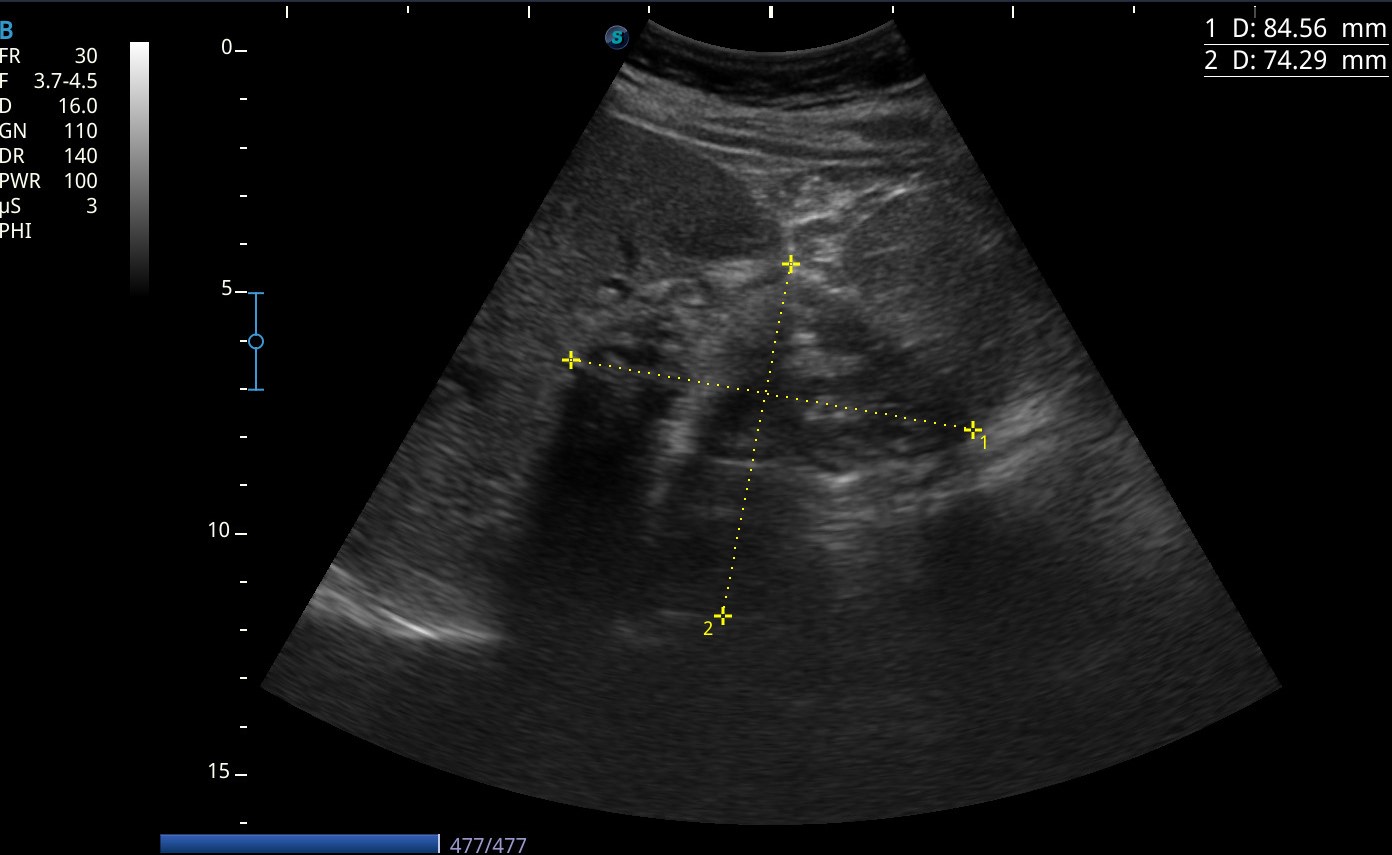

En la ecografía se observa una masa en lóbulo hepático derecho de paredes calcificadas y material heterogéneo hipoecogénico en su interior (8,1*7,6cm).

Se decide ampliar a TC abdominal que confirma el diagnóstico de quiste hidatídico hepático tipo IV.

Se determina que la placa pleural visualizada en la radiografía corresponde a la pared superior del quiste calcificado.